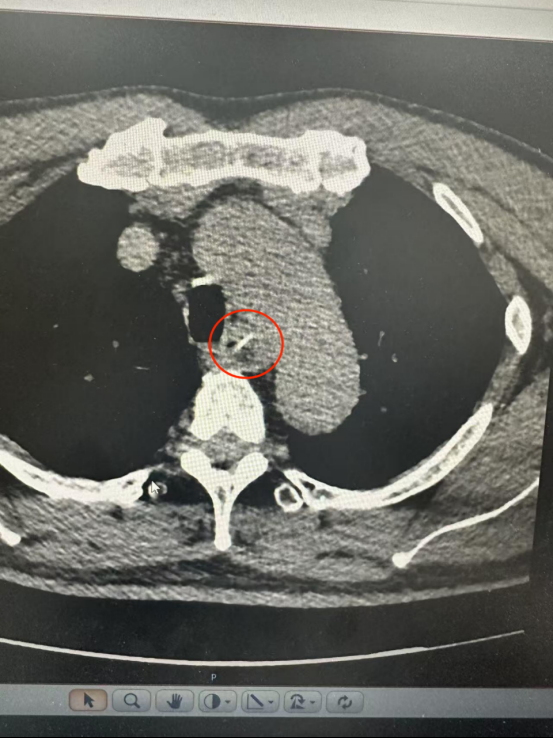

CT结果显示一根长约25毫米的鱼骨卡在食管中段,两端分别紧贴食管管壁外缘与主动脉弓内侧。主动脉是人体最粗大的动脉血管,鱼骨所处位置极为危险。

根据CT三维重建结果,鱼骨紧贴主动脉弓但未刺破主动脉及食管全层,尖端与主动脉切线垂直,呈“一”字型排列。